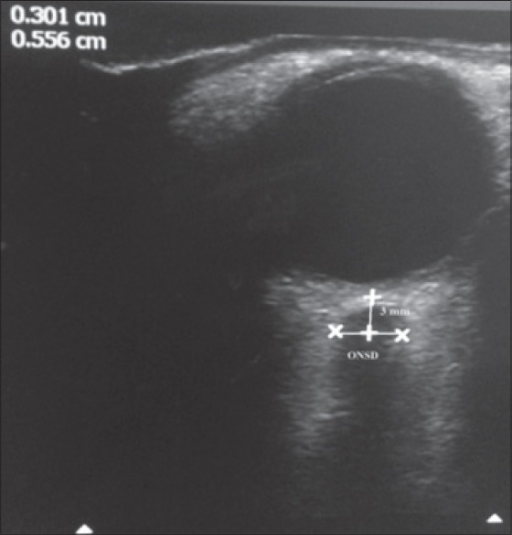

Optic nerve sheath diameter courtesy of OpenI

| current | 18:57, 16 June 2016 | ![]() | 512 × 535 (175 KB) | Neil.m.young (Talk | contribs) | Optic nerve sheath diameter courtesy of OpenI https://openi.nlm.nih.gov/detailedresult.php?img=PMC4548416_IJCCM-19-466-g001&query=nerve+sheath+ultrasound&it=xg&req=4&npos=4 |